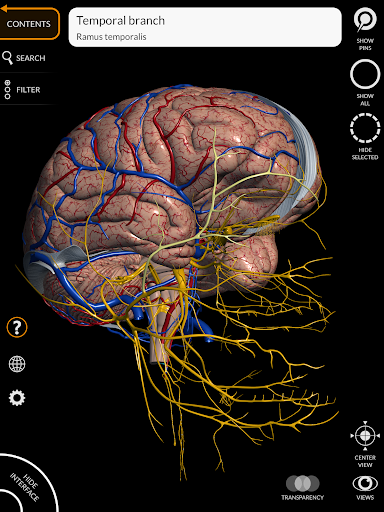

"Anatomy 3D Atlas" дозволяє легко та інтерактивно вивчати анатомію людини.

Завдяки простому та інтуїтивно зрозумілому інтерфейсу можна спостерігати кожну анатомічну структуру під будь-яким кутом.

Анатомічні 3D-моделі особливо деталізовані та мають текстури з роздільною здатністю до 4k.

Поділ за регіонами та попередньо визначені види полегшують спостереження та вивчення окремих частин або груп систем і зв’язків між різними органами.

• Нервова система

• Вибравши модель або шпильку, з’явиться відповідний анатомічний термін

• Анатомічні терміни та інтерфейс користувача доступні 11 мовами: латинською, англійською, французькою, німецькою, італійською, португальською, турецькою, російською, іспанською, китайською, японською та корейською

• Анатомічні терміни можуть відображатися двома мовами одночасно.